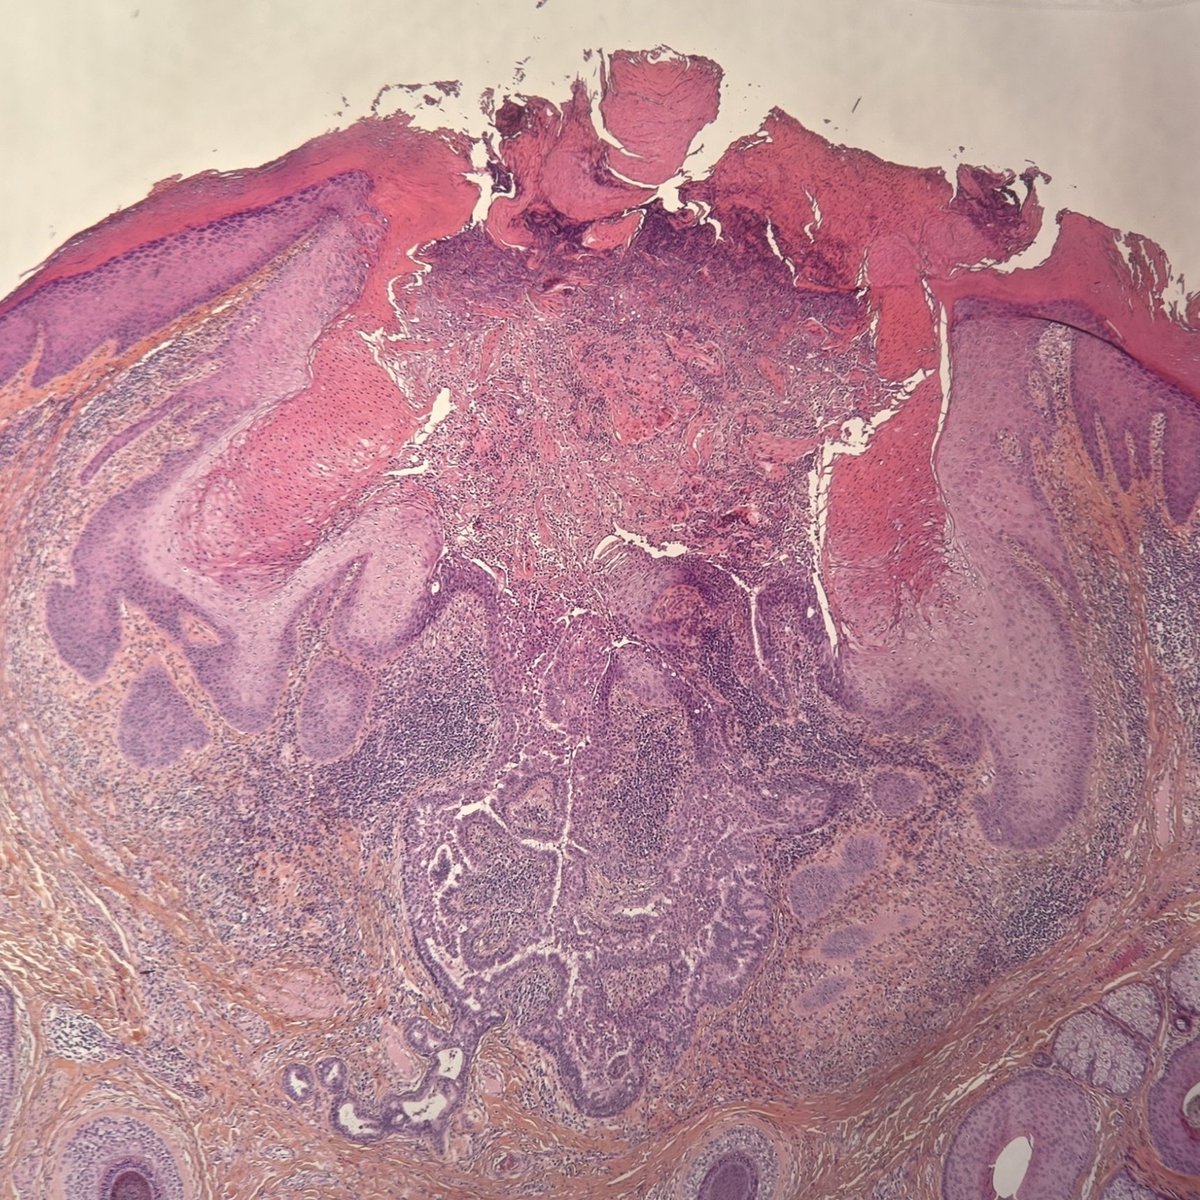

Syringocystadenoma papilliferum (SCAP) : ▫️Benign adnexal tumor ▫️cystic invaginations of the infundibular epithelium extending into the dermis with a double cell layer of inner columnar and outer cuboidal cells ▫️plasma cells are common in the stroma of each frond #dermopath